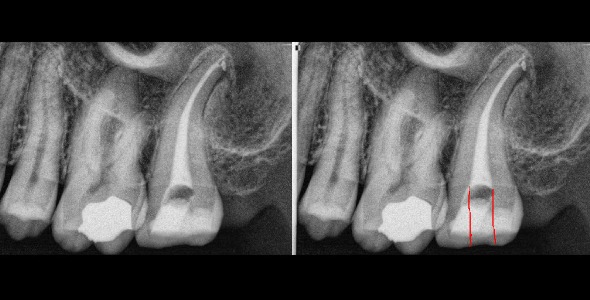

We all have been in countless situations where removing extra tooth structure is just an absolute necessity; you cannot treat what you cannot see. For example, maxillary second molars that are buccal and/or distally angulated. In these situations we will need to encroach upon the mesial marginal ridge, or the MB cusp, or the MP cusp in order to see (figure 3 and 4).

Figure 3: Here is a maxillary tooth #2 that I had to encroach upon the mesial marginal ridge more than I would have liked (red arrows). However there was such a limited mouth opening that the only way to reach and see the MB and MB2 canal was to remove more tooth upon the ridge.

Figure 4: Here is another 2nd molar tooth #15 in which I had to remove more mesial root structure than I would have liked. However the tooth was so long that in order to get access to the apex I needed to use a longer rotary file set which meant that I needed to tild the access towards the mesial so that the longer file would fit. On the right side I have drawn in red where I feel the ideal spot for access would be placed which is more centered.